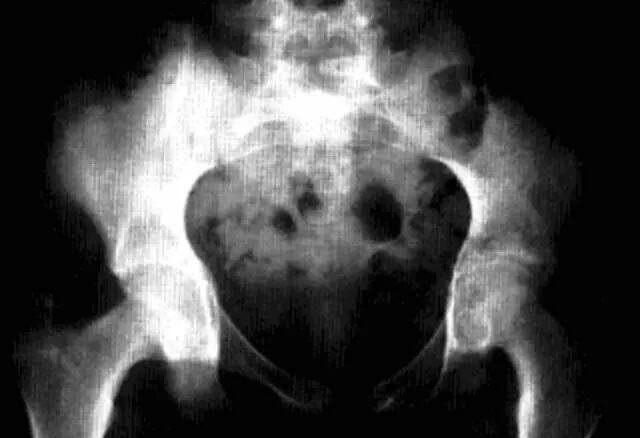

影像诊断:X线片为主要检查手段,MRI能显示早期髋关节改变。

1、平片:双侧对称受累,早期骨质疏松,关节囊膨隆,股骨头及髋臼骨质侵蚀糜烂;中期关节间隙一致性狭窄,软骨下囊性变,关节面边缘骨质增生,坐骨结节、坐骨耻骨支及股骨大转子可伴骨膜炎;晚期股骨头内移、髋臼内突,关节腔闭锁呈骨性强直。

2、CT:早期少量关节腔积液,可伴髂腰肌囊扩张,同时股骨头骨质疏松,股骨头及髋臼缘囊状、虫蚀状骨质缺损;中期关节面边缘硬化、囊变、骨赘形成,股骨头基底滑膜附着处增生,髋关节间隙均匀一致性狭窄消失,双侧髋对称性骨性强直,股骨头及髋臼可普遍性肥大。

3、MRI:①关节积液,关节间隙增宽,②滑膜增厚,增强后明显强化,③关节软骨水肿,④关节面软骨信号改变,炎性血管翳增生,信号强度不均,⑤软骨下囊性变,⑥关节骨性强直。